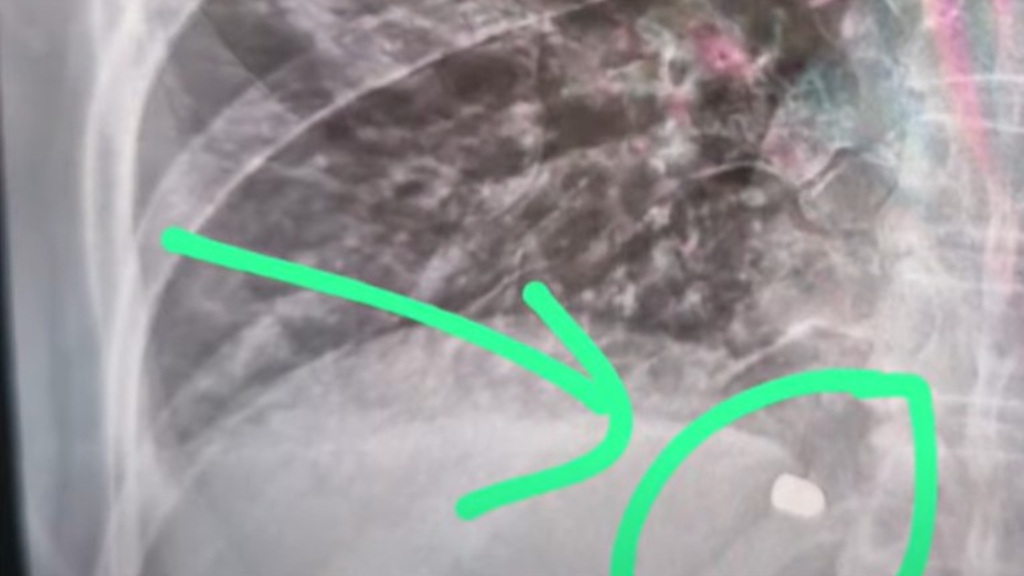

Martín, el marido de Ana, relató: «Ella está vida de milagro, la bala calibre 22 le perforó un pulmón. Ya ha habido gente que me dijo que tuvieron problemas en el mismo lugar. Los investigadores me dijeron que están haciendo todo lo posible. Lo que pasó es una locura».